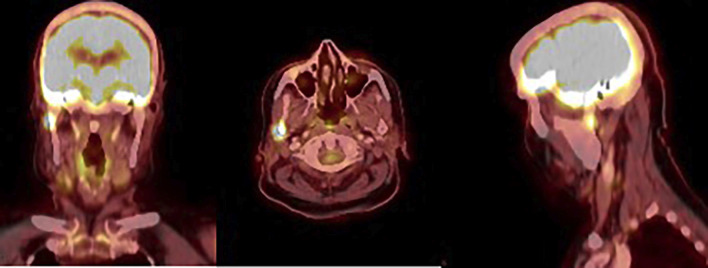

Case report: An 86-year-old woman with a history of oncocytic thyroid carcinoma treated with total thyroidectomy and radioactive iodine in 2019. During follow-up, elevated thyroglobulin levels were detected, and a PET-CT scan revealed uptake in the right mandibular condyle. The lesion was confirmed by magnetic resonance imaging and surgical biopsy and was treated with a right condylectomy. Histopathological analysis revealed bone infiltration by oncocytic carcinoma. The patient had a favorable postoperative course, with undetectable serum thyroglobulin levels after surgery.